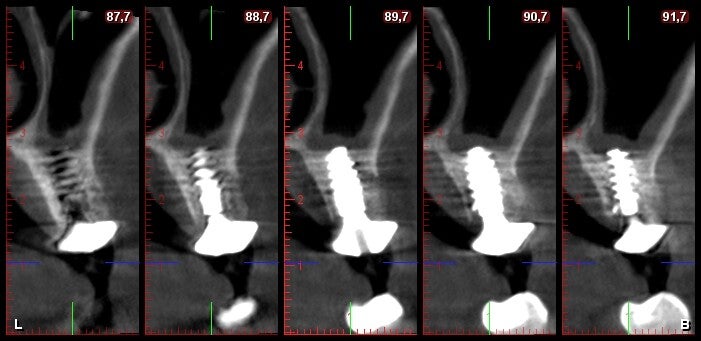

Rehabilitación de atrofias severas tanto maxilares como mandibulares mediante Implantes Cigomáticos e Implantes Personalizados Subperiósticos